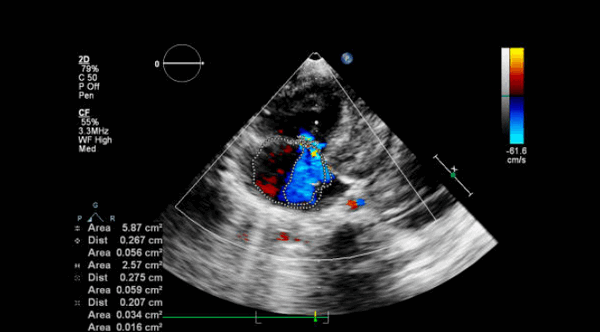

Эхокардиография и цветное допплеровское картирование

![Эхокардиография после протезирования клапанов]()

Допплер-эхокардиография позволяет выявить скорость потока через протез клапана, что позволяет определять градиенты давления с использованием модифицированного уравнения Бернулли (градиент давления = 4 х скорость в квадрате). Отличная корреляция была установлена между допплеровским методом и инвазивным измерением давления двойным катетером, выполненным одновременно на различных протезированных клапанах. Однако, несколько моделей инвитро показали завышение градиента на аортальном протезе, которые определяются по допплеровским скоростям по сравнению с катетер-производными градиентами. Расхождение данных меньше в протезе с большим опорным кольцом. Потенциальные источники в разнице между допплер-производными и катетер-производными перепадами давления на протезах должны быть учтены, но это не является большой проблемой в выявлении дисфункции протеза.

Непрерывно-волновая допплерография может быть использована для оценки функциональной площади отверстия протеза аортального и митрального клапанов. Время полуспада давления (РНТ) метод, используемый для определения стеноза нативного митрального клапана, обычно переоценивает площадь митрального протеза. Протез клапана изначально стенотический в разной степени по сравнению с соответствующим родным клапаном, поэтому скорость потока через нормальный протез клапана выше, чем ожидаемый на родном клапане. Нормальная скорость протезного потока (следовательно, максимальный и средний градиенты давления) зависит от типа и размера протеза, его расположения и сердечного выброса. Следовательно, очень важно знать нормальные диапазоны скоростей потока для определенных типов протезов для сравнения с измеренными значениями. Поскольку гемодинамика протеза зависит от различных факторов, рекомендуется выполнить базовое допплеровское эхокардиографическое исследование в раннем послеоперационном периоде (сделать «отпечаток» функции протеза), так что он может быть использован в качестве эталона для сравнения с последующими исследованиями. Обе ситуации как регургитация, так и обструкция может привести к увеличению скорости потока через протез. Увеличение скорости потока указывает на то, что имеется несоответствующее меньшее отверстие, когда в протезе есть препятствие и при этом нет клинически значимой регургитации или увеличивается объем потока через протез (есть значимая регургитация).

Другие полезные характеристики допплеровского исследования на эхокардиографии протезов позволяет отличить непроходимость от регургитации. Когда на протезе имеется препятствие, кроме увеличения скорости потока пролонгируется длительность период полуспада РНТ (для протезов митрального и трикуспидального клапана). Увеличение скорости потока через обструкцию аортального протеза не сопровождается увеличением скорости в выходном тракте левого желудочка (ВТЛЖ), но увеличивается при тяжелой регургитации. Когда скорость через митральный или трехстворчатый протез в диастолу увеличивается из-за сильной регургитации, РНТ является нормальным или укороченным, а в ВТЛЖ скорость уменьшается, потому что прямоток из-за регургитации в систолу через протез уменьшается (часть крови попадает обратно в предсердие). Состояние высокого сердечного выброса увеличивает скорость на протезе, и это может быть подтверждено путем записи увеличение скорости потока во всех кардиальных отверстиях (ВТЛЖ, атриовентрикулярных клапанах, выходном тракте правого желудочка).